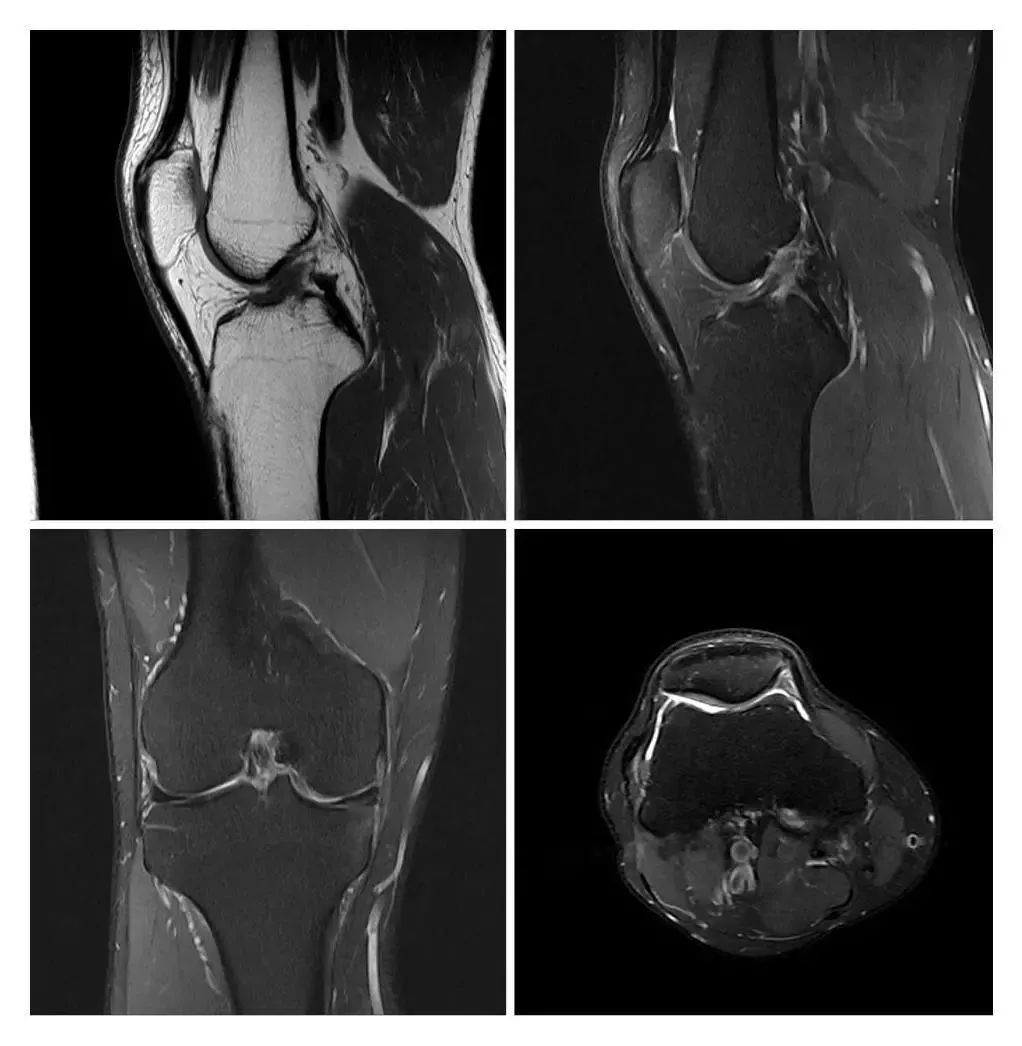

MRI現(xiàn)已應(yīng)用于全身各系統(tǒng)的成像診斷。效果最佳的是顱腦,及其脊髓、心臟大血管、關(guān)節(jié)骨骼、軟組織及盆腔等。而且不同于已有的成像術(shù),它對疾病的診斷具有很大的潛在優(yōu)越性。多序列成像、多種圖像類型,為明確病變性質(zhì)提供更豐富的影像信息,能很好的滿足臨床的診斷需求。

滑動查看更多